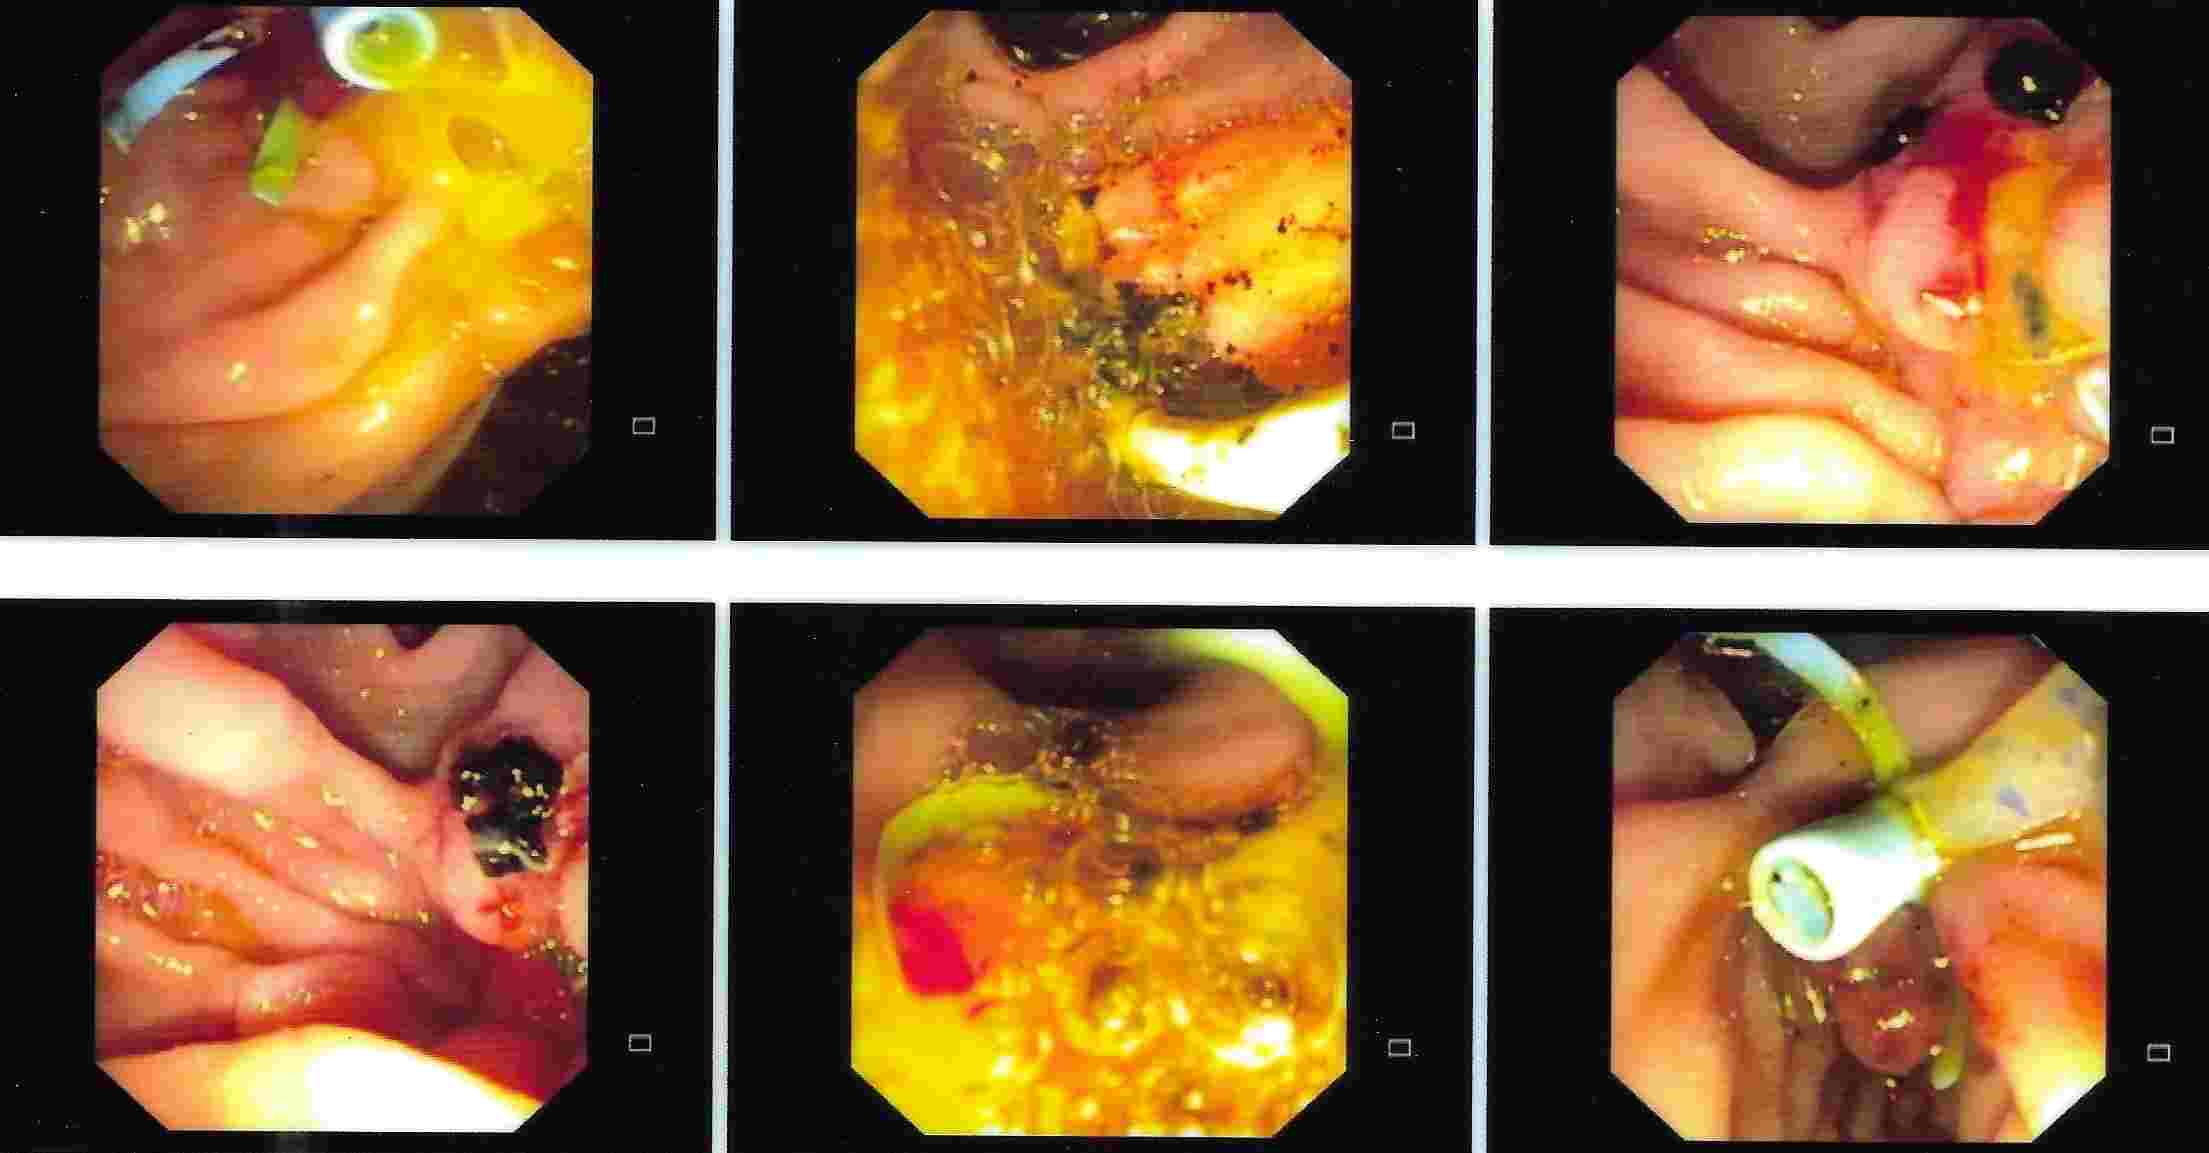

GALL BLADDER STONES TREATMENT

Endoscopic Retrograde Cholangio Pancreatography is an advanced endoscopic procedure related to

diseases of pancreas and biliary tree. Common indication for ERCP is jaundice due to obstruction

of biliary tube, which drains the bile from the liver into the intestine.

Obstruction can be due to a gallstone, which has slipped into bile tube and has blocked the bile tube.

These Stones can be removed by ERCP, without any surgery being involved.

This procedure is necessary if the patient has stones in the gallbladder and also in bile tube and

is always performed before Laparoscopic removal of gallbladder. Cancer of the gallbladder, biliary tree, pancreas,

duodenum or obstruction by lymph nodes can be responsible for jaundice and can be very effectively

treated by ERCP without any need for surgery.

This technique is important in these conditions as majority of the patients coming for jaundice are at an advanced stage of cancer and need palliative treatment to give relief from severe itching and jaundice. Infection or narrowing in the biliary tree can be treated by ERCP.

Common Biles Duct Stones

Common Biles Duct Stones

Cancer of the Bile Tube in Duodenum

Impacted Stone in Common Bile Duct

Chronic Pancreatitis is condition which can result in recurrent attacks of persistent and severe pain.

This can be due to presence of stones or narrowing of the pancreatic duct and can be treated by ERCP.

Pancreatic pseudocyst / collection of fluid is a complication of pancreatitis, which results

in abdominal pain, vomiting, fever etc. It is a serious condition which can be treated by ERCP.

Treatment of Chronic Pancreatitis by Stent

Most of the lesions of biliary system and pancreas were treated earlier by surgery with its own complications, but now with ERCP these conditions can be treated without any surgery and morbidity and mortality related to surgery, and as a cheaper option for surgery and has become treatment of choice for the same.